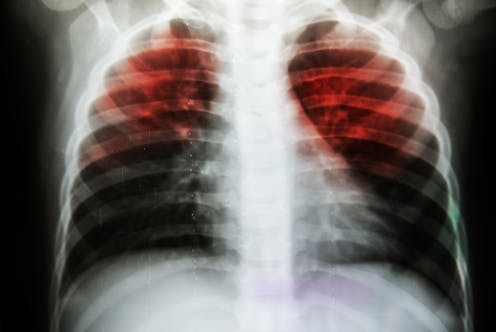

Tuberculosis is caused by a bacterium, called Mycobacterium tuberculosis, which causes a lung infection that progresses slowly but can destroy the lungs if not treated. Although we might not think of it too often here in the United States, it remains a major killer worldwide. In 2018 alone, there were 10 million new cases of active TB and almost 1.5 million deaths from TB infections. What makes the disease particularly insidious is that because symptoms are slow to manifest and can resemble other diseases, it takes a long time before people with TB are diagnosed and given treatment. But until a person with TB gets treated with drugs, they can pass it on to other people - and this bacterium spreads fast through coughing, sneezing, and even singing.

The IV vaccine provided incredible protection. In most of the animals, there were no M. tuberculosis bacteria in the entire monkey. We also used specialized imaging, called PET-CT, and showed that the lungs of most of these monkeys were free of any disease. This means that BCG vaccine prevented TB infection and disease when given intravenously.